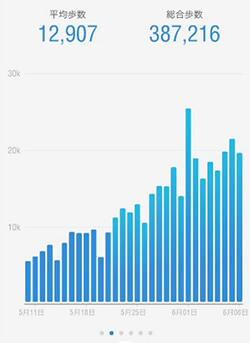

Takatoshi.T様 50歳

足を引きずらないと歩けない…

医師には150万の手術を勧められる…

そんな私でも1回で痛みが激減!

翌日にはスムーズに歩けるようになり、

私も職場の仲間もビックリでした!

重度の椎間板ヘルニアに悩まされていました。

病院では椎間板ヘルニアと診断された。

「足を引きずらないと歩けない」「脚が痛くて夜も眠れない」「まっすぐ歩けない」など…

重度の椎間板ヘルニアで悩んでいました。整体・接骨院・鍼などすべて受けましたが治らず、あきらめかけていました。整形外科では、神経ブロック注射を2回打っても改善の兆しはなし。

ヘルニアを摘出するしかないと思い、あきらめ半分で手術の専門病院に足を運ぶと…

レントゲンとMRIの検査だけで「ヘルニアがあるから手術ね」と告げられてしまったんです。

私の身体に触れもせずあっさり手術宣告(しかも、手術費用は150万円)されてしまい、「このままではいけない!」と一念発起して、

もう一度自分に合った治療はないかと探しました。

そこで遂にAKS療法®に辿り着きました。

「これが最後の賭けだ。」そんな思いで山内先生の治療を受けることに。

寝返りができない、朝起きたら足を引きずって腰も曲がっていた…

そんな状態でしたが、嘘のように症状が改善されていきました。

治療を受けた翌日には痛みが劇減して、

普通に日常生活を送れるようになってしまったので驚きましたよ。

職場でも急に私の歩きが改善したので、みんなに驚かれています。

普通の生活を取り戻してくれた山内先生とAKS療法®には感謝しかありません。

あと、この治療を受ける前は1日3回ロキソニンを飲んでいたんですよ。

夜なんて、ロキソニンを飲まないと痛みで眠れませんからね。

でも、この治療を受けてからは、ロキソニンを飲まなくてもぐっすり眠れるようになりました!

手術はお金だけではなく、体も傷つけるし副作用も心配だったので、

それ以外の方法を探していました。

手術宣告された椎間板ヘルニアでも、

正しい施術をすればたった1回で劇的に改善することを皆さんに知って欲しいです!

私の臨床事例が、同じ悩みで苦しむ方の希望になればと思います。